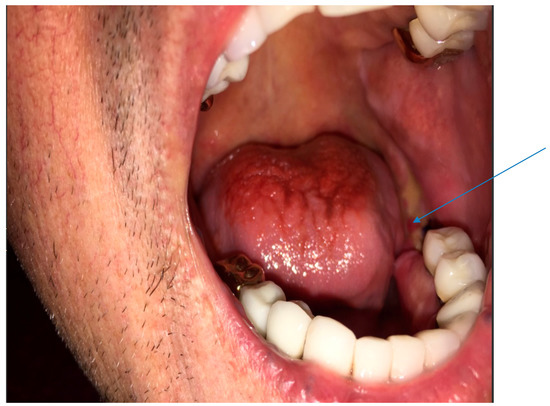

Computerized tomography maxillofacial imaging showed a lytic lesion in left ramus of the mandible with loss of bone matrix (Figure 2). Chest radiograph was completely normal. Differential diagnoses considered in addition to actinomycosis included nocardiosis, tuberculosis, osteosarcoma of the mandible and endemic fungal infections.

Figure 2.

Maxillofacial computerized tomography imaging showing a lytic lesion in left ramus of the mandible with loss of bone matrix (see arrow).